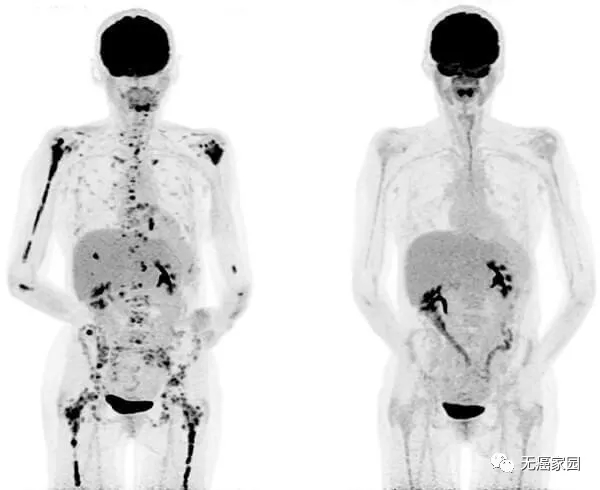

使用靶向 BCMA 的 CAR T 细胞治疗多发性骨髓瘤患者的 PET 扫描之前(左)和之后(右)。图片来源:国家癌症研究所